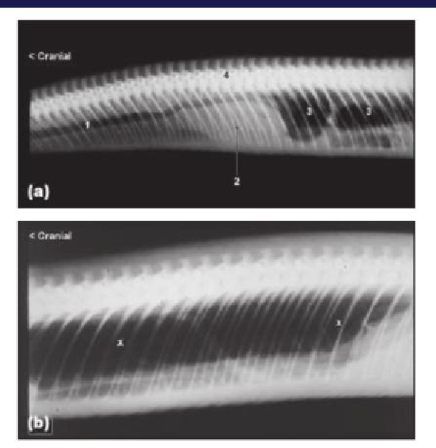

How do we perform a radiograph on a snake

use a doppler to identify where the heart is

use this as a guid for positioning for radiograph

Snakes also have air sacks